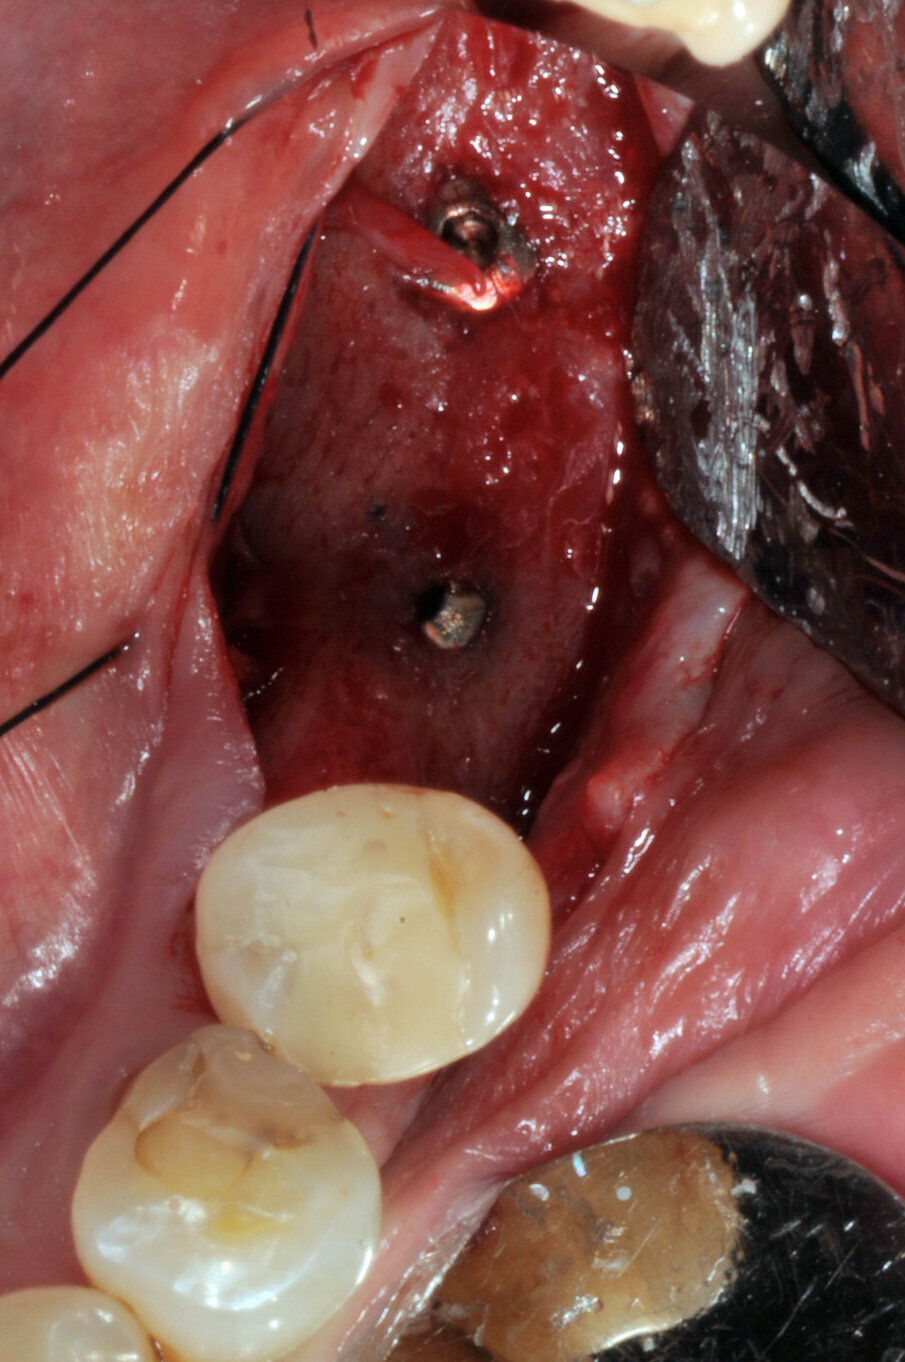

Il giorno della chirurgia fu somministrata una terapia antibiotica profilattica, per mezzo di amoxicillina più acido clavulanico, della durata di sei giorni. Dopo somministrazione di anestesia locale con Articaina al 2% 1:100000, fu eseguita un’incisione crestale estesa nel solco del dente 35 senza incisioni di rilascio. Furono eseguite le osteotomie a bassi numeri di giri senza irrigazione come da protocollo BTI e furono inseriti due impianti BTI CORE 4,5X3,75. Al di sopra degli impianti fu collocato osso di recupero dalla fresatura mischiato con PRGF e il tutto fu protetto da due membrane di fibrina ottenute per centrifugazione del sangue della paziente con tecnica Endoret PRGF. Furono applicate suture a punti staccati con filo Supramid Braun 5.0 (Figg. 5-7).